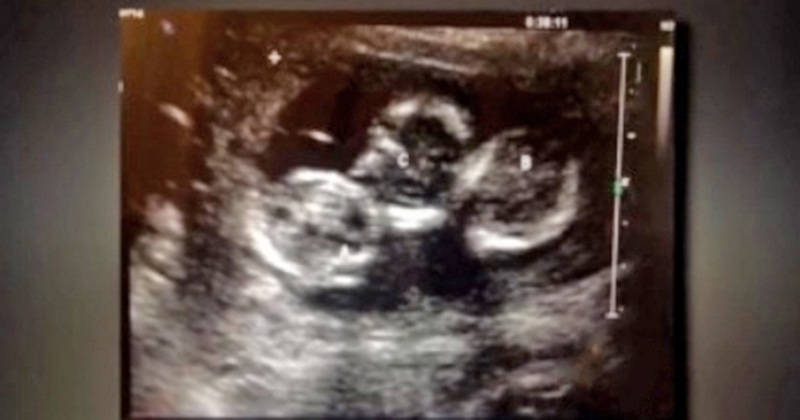

სტეფანი და ბრედი ამერიკელი ცოლ-ქმარი არიან, რომელთაც 2 წლის წინ ტყუპები შეეძინათ. როდესაც სტეფანი ექიმთან იყო მისული გაიგო, რომ ორ პატარას ელოდა, მაგრამ რამდენიმე კვირაში კიდევ ერთხელ მისულ ქალს ექიმმა უთხრა, რომ მის მუცელში მესამე პატარაც იყო, რაც ძალიან იშვიათობაა და მილიონში ერთ ქალს შეიძლება დაემართოს.

ქალმა იმშობიარა 2014 წლის 1 დეკემბერს.